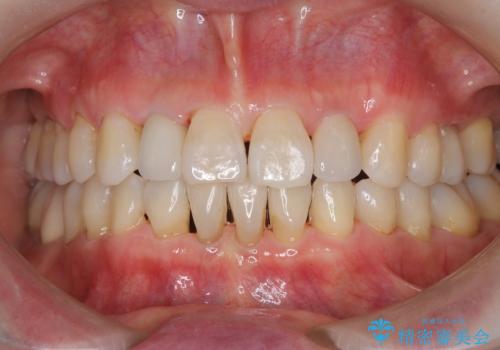

前歯をきれいにしたい オールセラミッククラウンにによる補綴